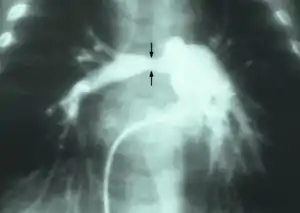

| Stenosis of the right pulmonary artery in a patient which was due to a case of congenital rubella. | |

Angiogram showing bilateral origin stenoses of pulmonary artery branches